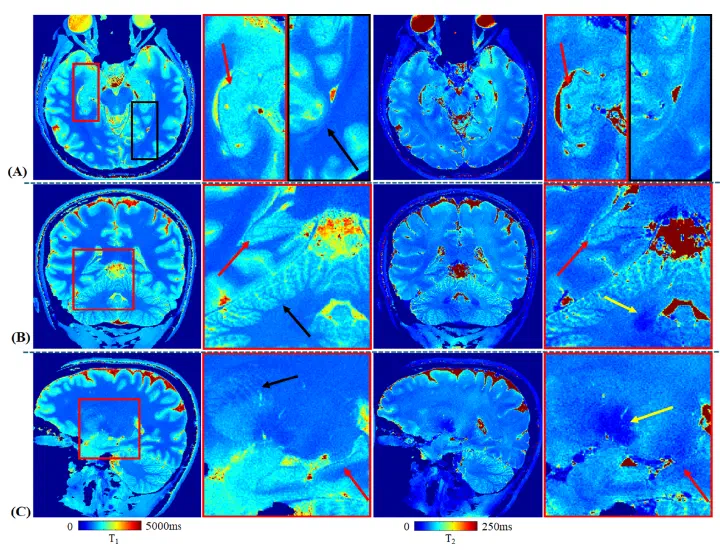

In vivo meso-scale whole-brain quantitative imaging with tailored MRF on the NexGen 7T scanner